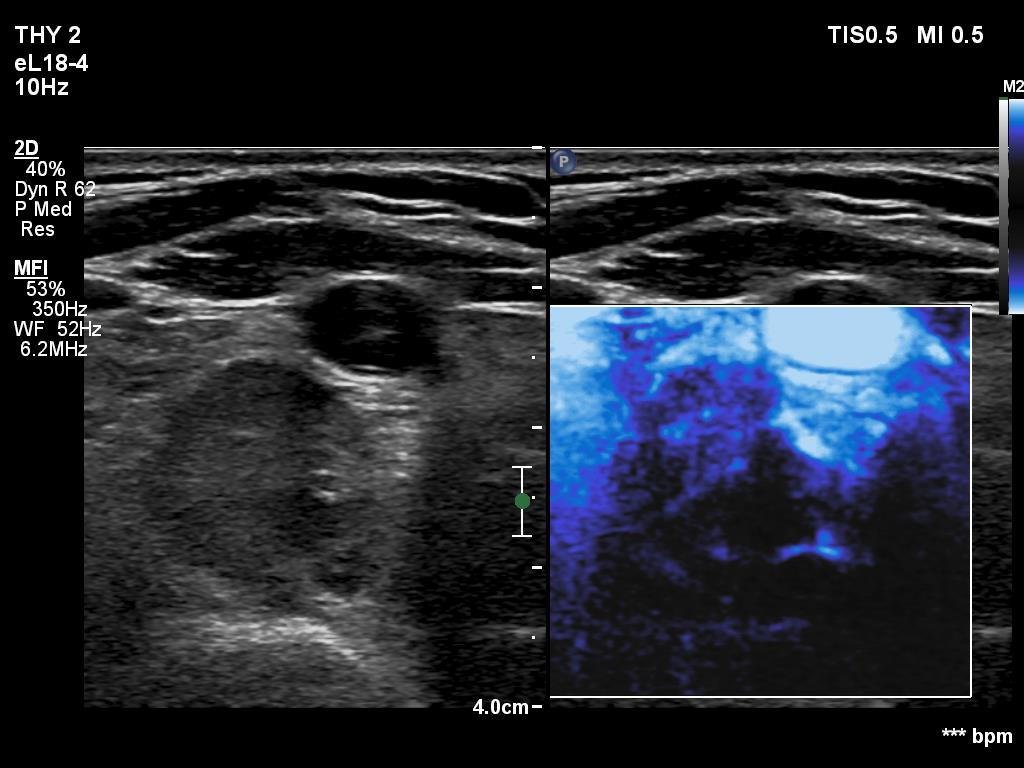

Follow-up investigation 6 months after first visit (ultrasonographic picture 8)

Lower and dorsal to the right lobe, transverse scan, microflow imaging. This pattern is not specific.